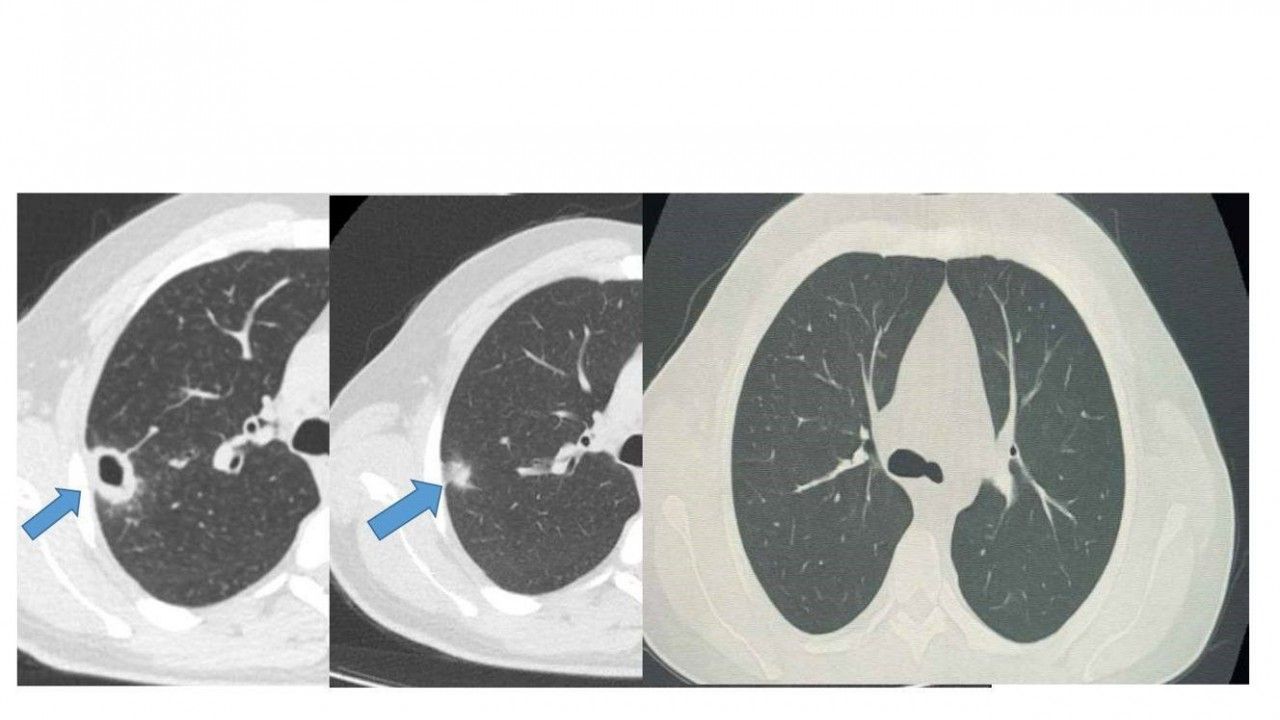

Bayburt Devlet Hastanesine öksürük ve balgam şikayetiyle başvuran 50 yaşındaki hastanın akciğerinde kitle benzeri bir doku tespit edildi. Yapılan tetkikler sonucu ciddi bir hastalık olmadığı belirlenen hasta, erken tanı ve doğru tedavi sayesinde sağlığına kavuştu.

İki haftalık tedavi sürecinin sonunda yapılan kontrollerde lezyonun neredeyse tamamen gerilediği görüldü. Sağlığına kavuşan hastanın taburcu edildiği ve durumunun iyi olduğu öğrenildi.